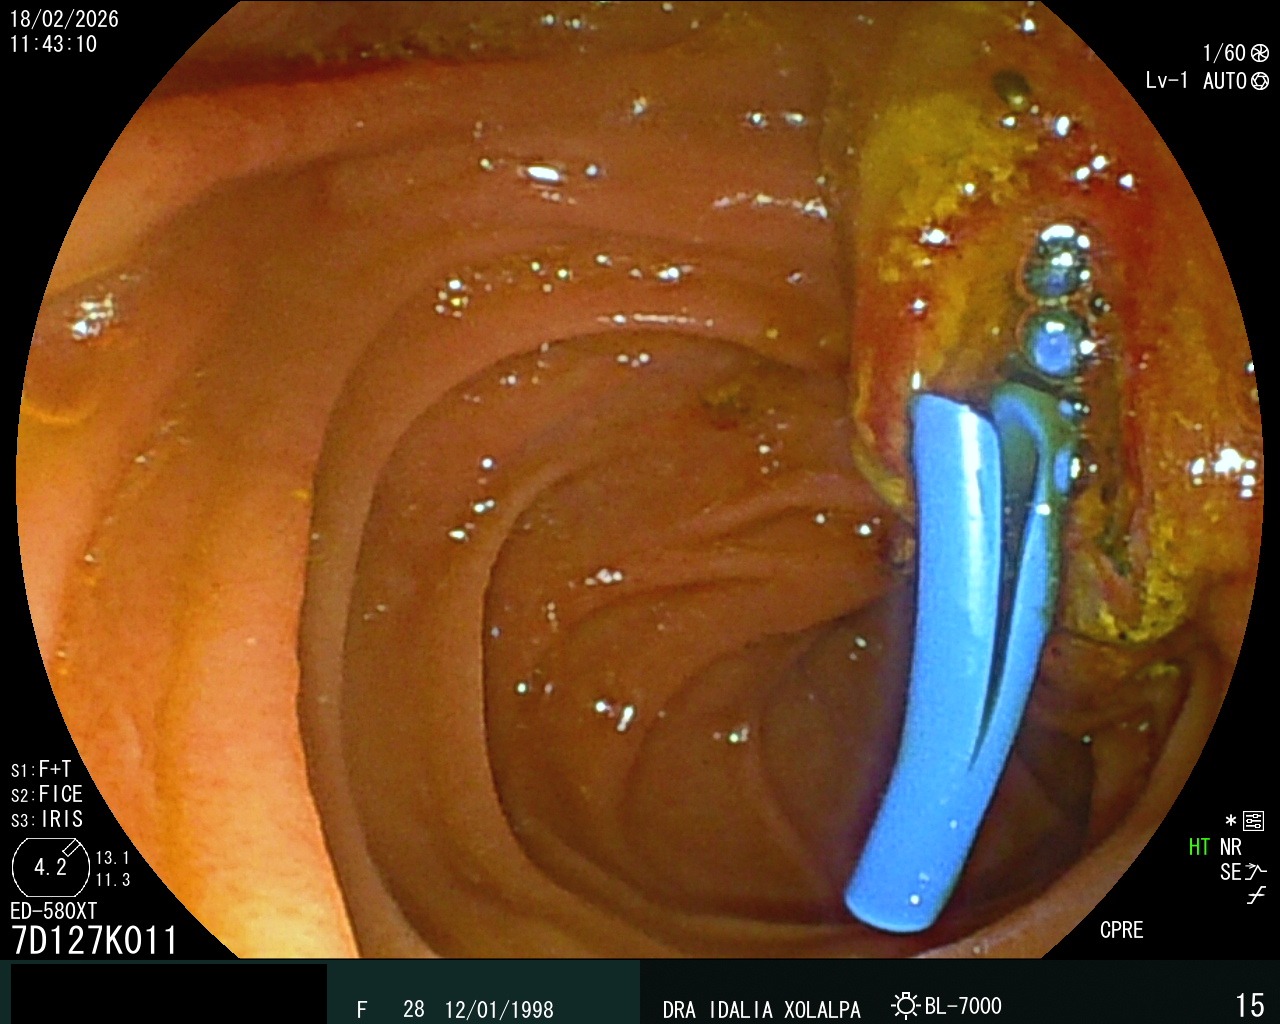

CPRE

Colangiopancreatografía Retrógrada Endoscópica

Prótesis Biliar

Colocación de prótesis biliar por CPRE